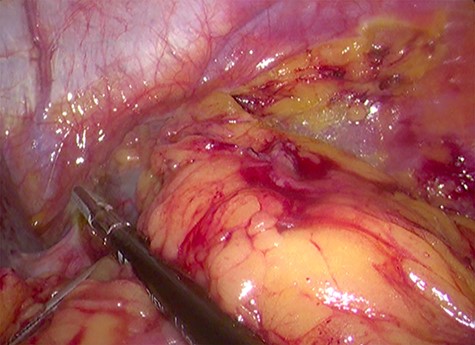

Because of its relatively large size and the patient’s request, he underwent a laparoscopic transperitoneal left adrenalectomy in the right lateral decubitus position (two 10-mm and one 5-mm ports). Intraoperatively, an enlarged left adrenal gland and a cystic lesion closely adherent to it were found, surrounded by adipose tissue (Figs 3 and 4). They were completely resected en bloc and removed in the endobag. No adverse events occurred postoperatively and he was discharged on Day 3.

Laparoscopic view of the retroperitoneal space containing the left adrenal gland and a cystic lesion surrounded by large amounts of adipose tissue.